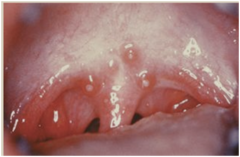

-Staphylococcus pyogens and other bacteria and virus -Enlarged tonsils mucosal erythema